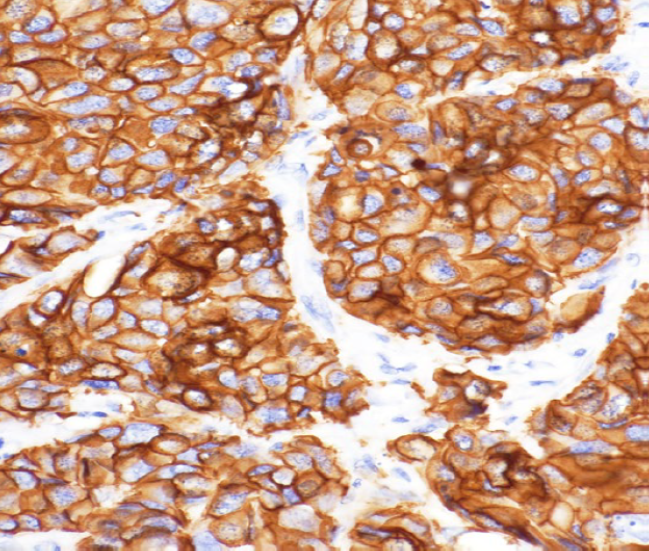

樣品:HE染色結腸